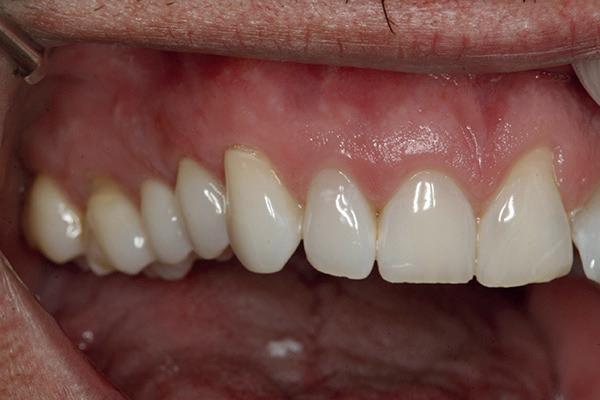

Un pacient caucazian în vârstă de 77 ani s-a prezentat la clinica autorului după cinci ani în care nu a fost la niciun control stomatologic. Examinarea clinică a arătat o pierdere semnificativă de os, parodontită cronică și multiple edentații care au destabilizat ocluzia. Pacientul a raportat sensibilitate la rece la nivelul primului molar drept inferior nr. 46, în special la ingerarea de lichide reci. Radiografia periapicală a confirmat constatările examenului clinic; în

plus, s-a detectat și prezența unei carii radiculare la nivelul rădăcinii distale a aceluiași molar, cu răspuns pozitiv la testul de sensibilitate (fig. 1-2).

1. Situația clinică inițială.